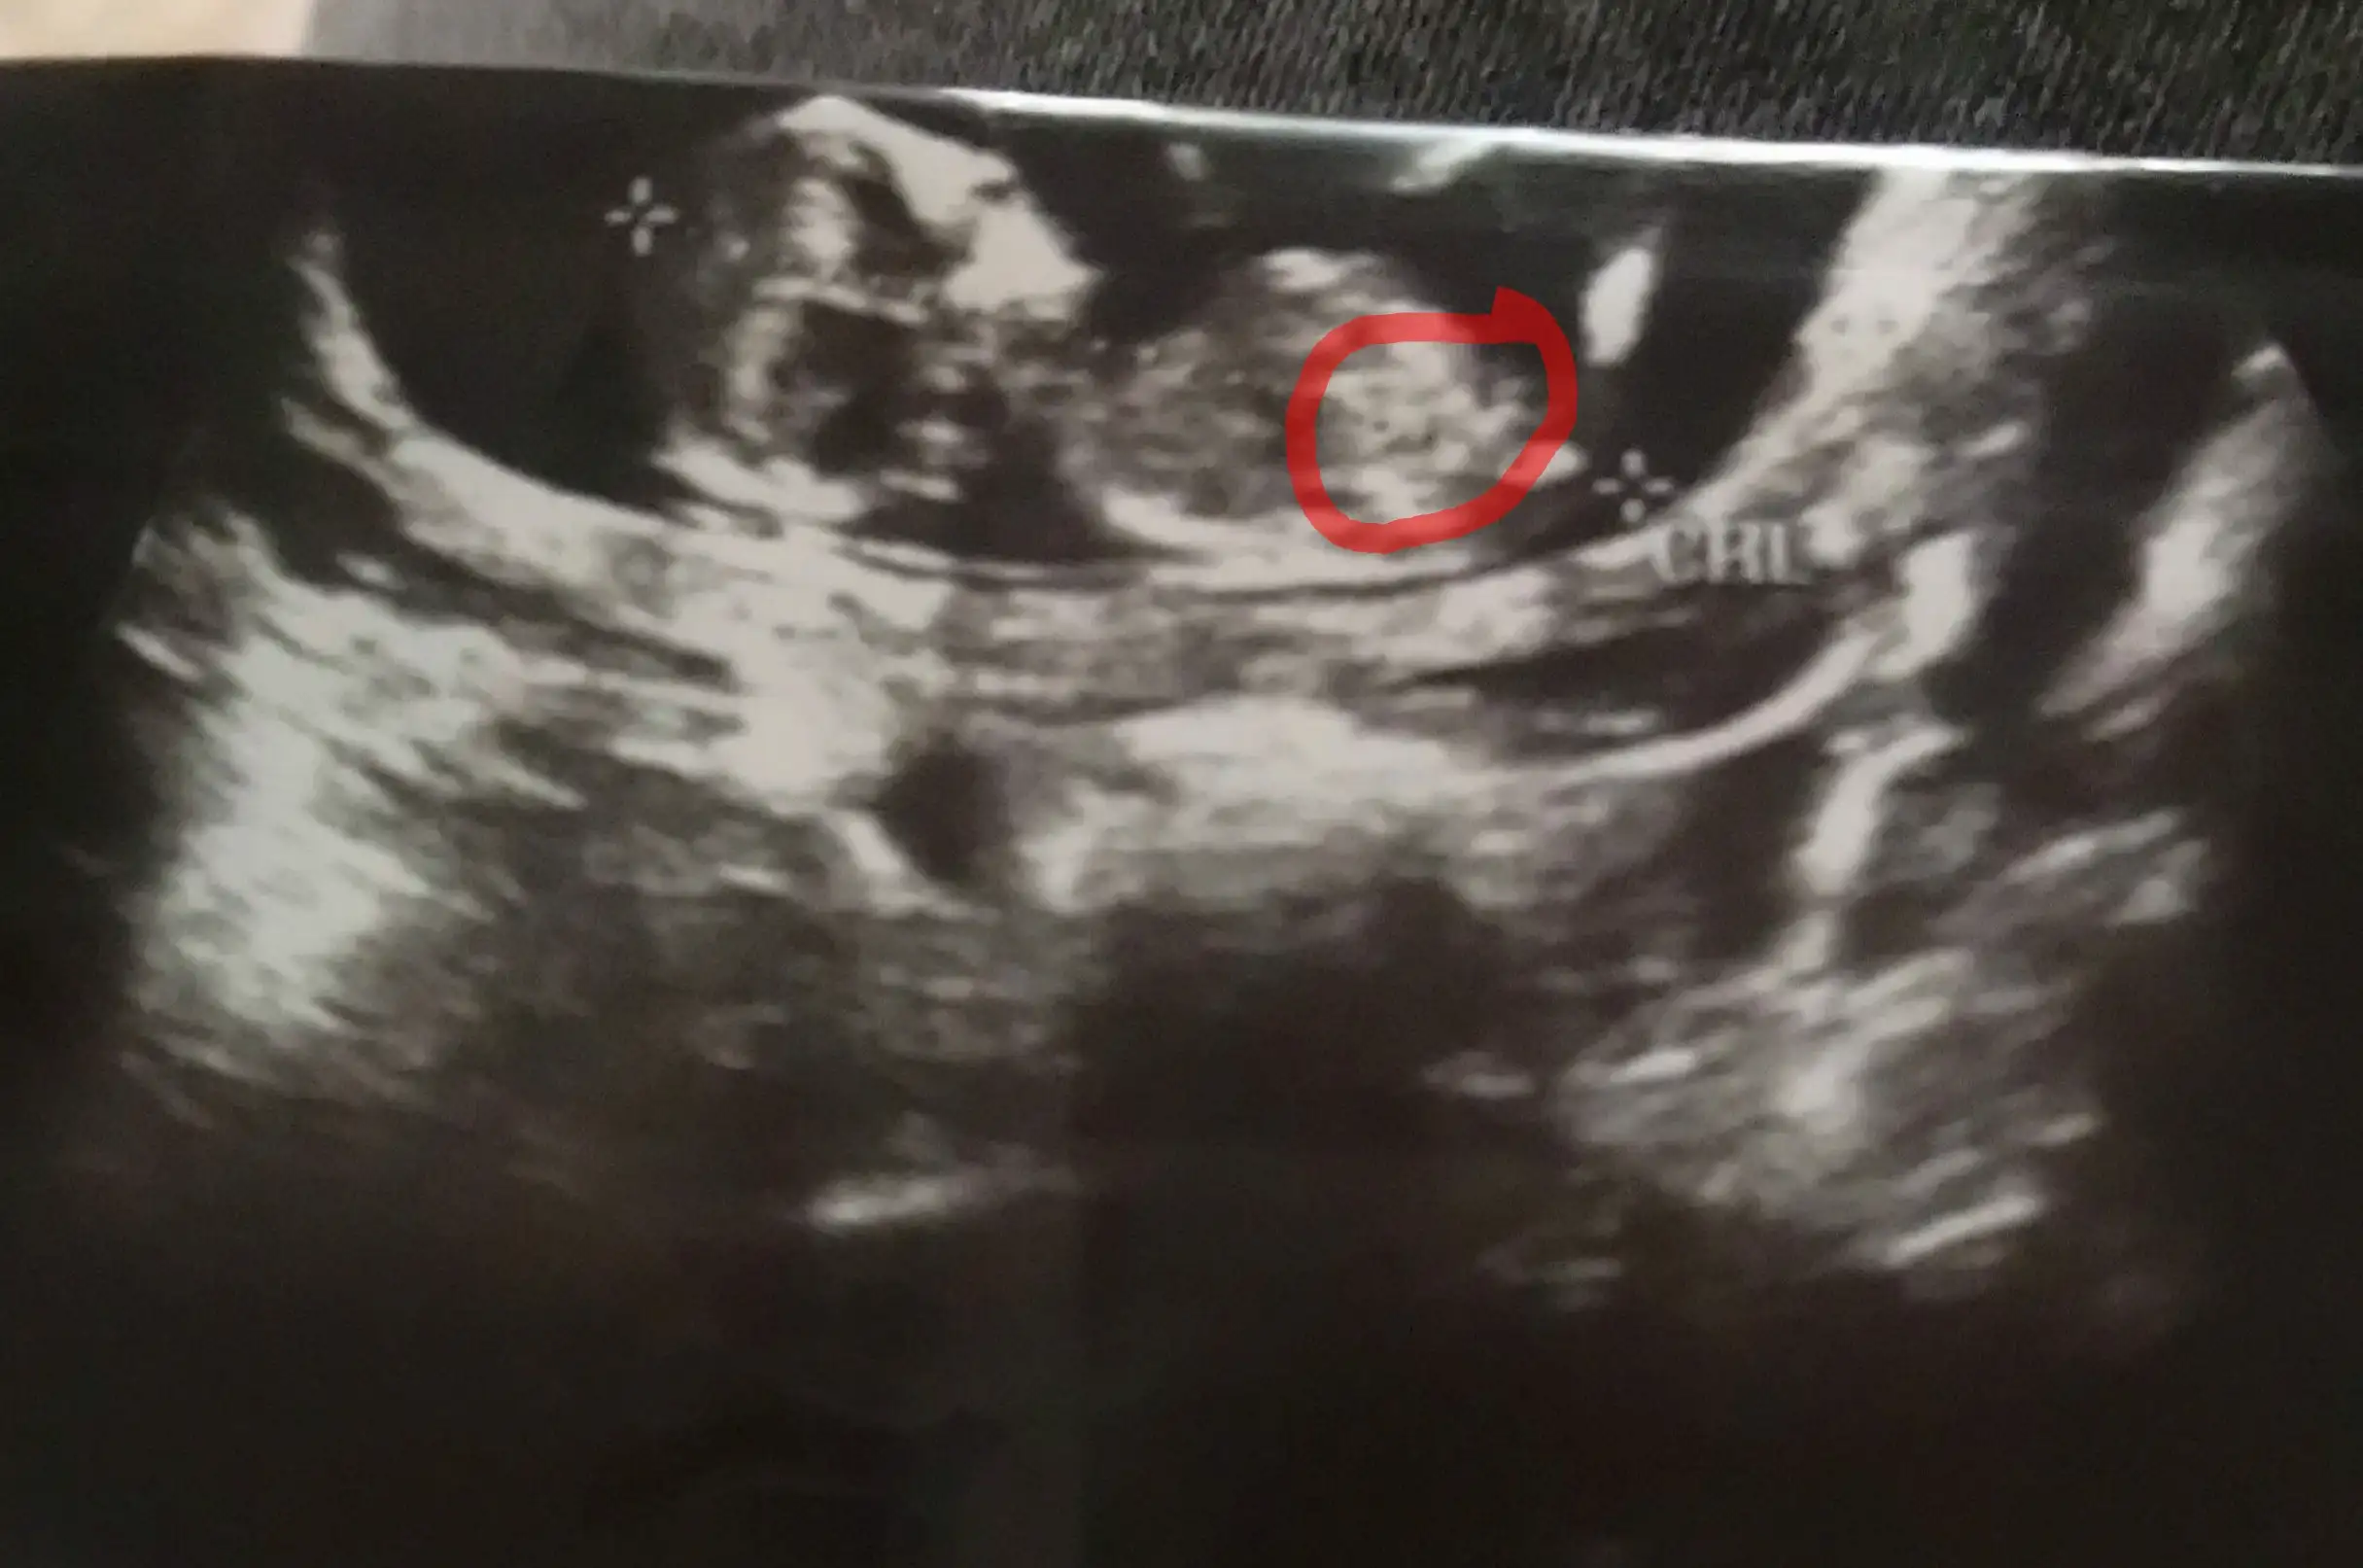

Nubtan anlamayan ben bile gördüysem Allah’ın izniyle kesin erkektir inşallah inşallah sağlıkla kucağına alırsınBuda şimdiki hamileliğim işaretlediğim yer nubsa erkeğe uyuyor, daha cinsiyet öğrenmedik

Yöntem denemiş miydin cnm? Okadar çok sayfa varki kim ne uygulayıp erkeğe hamile kalmış çözemedimBuda şimdiki hamileliğim işaretlediğim yer nubsa erkeğe uyuyor, daha cinsiyet öğrenmedik